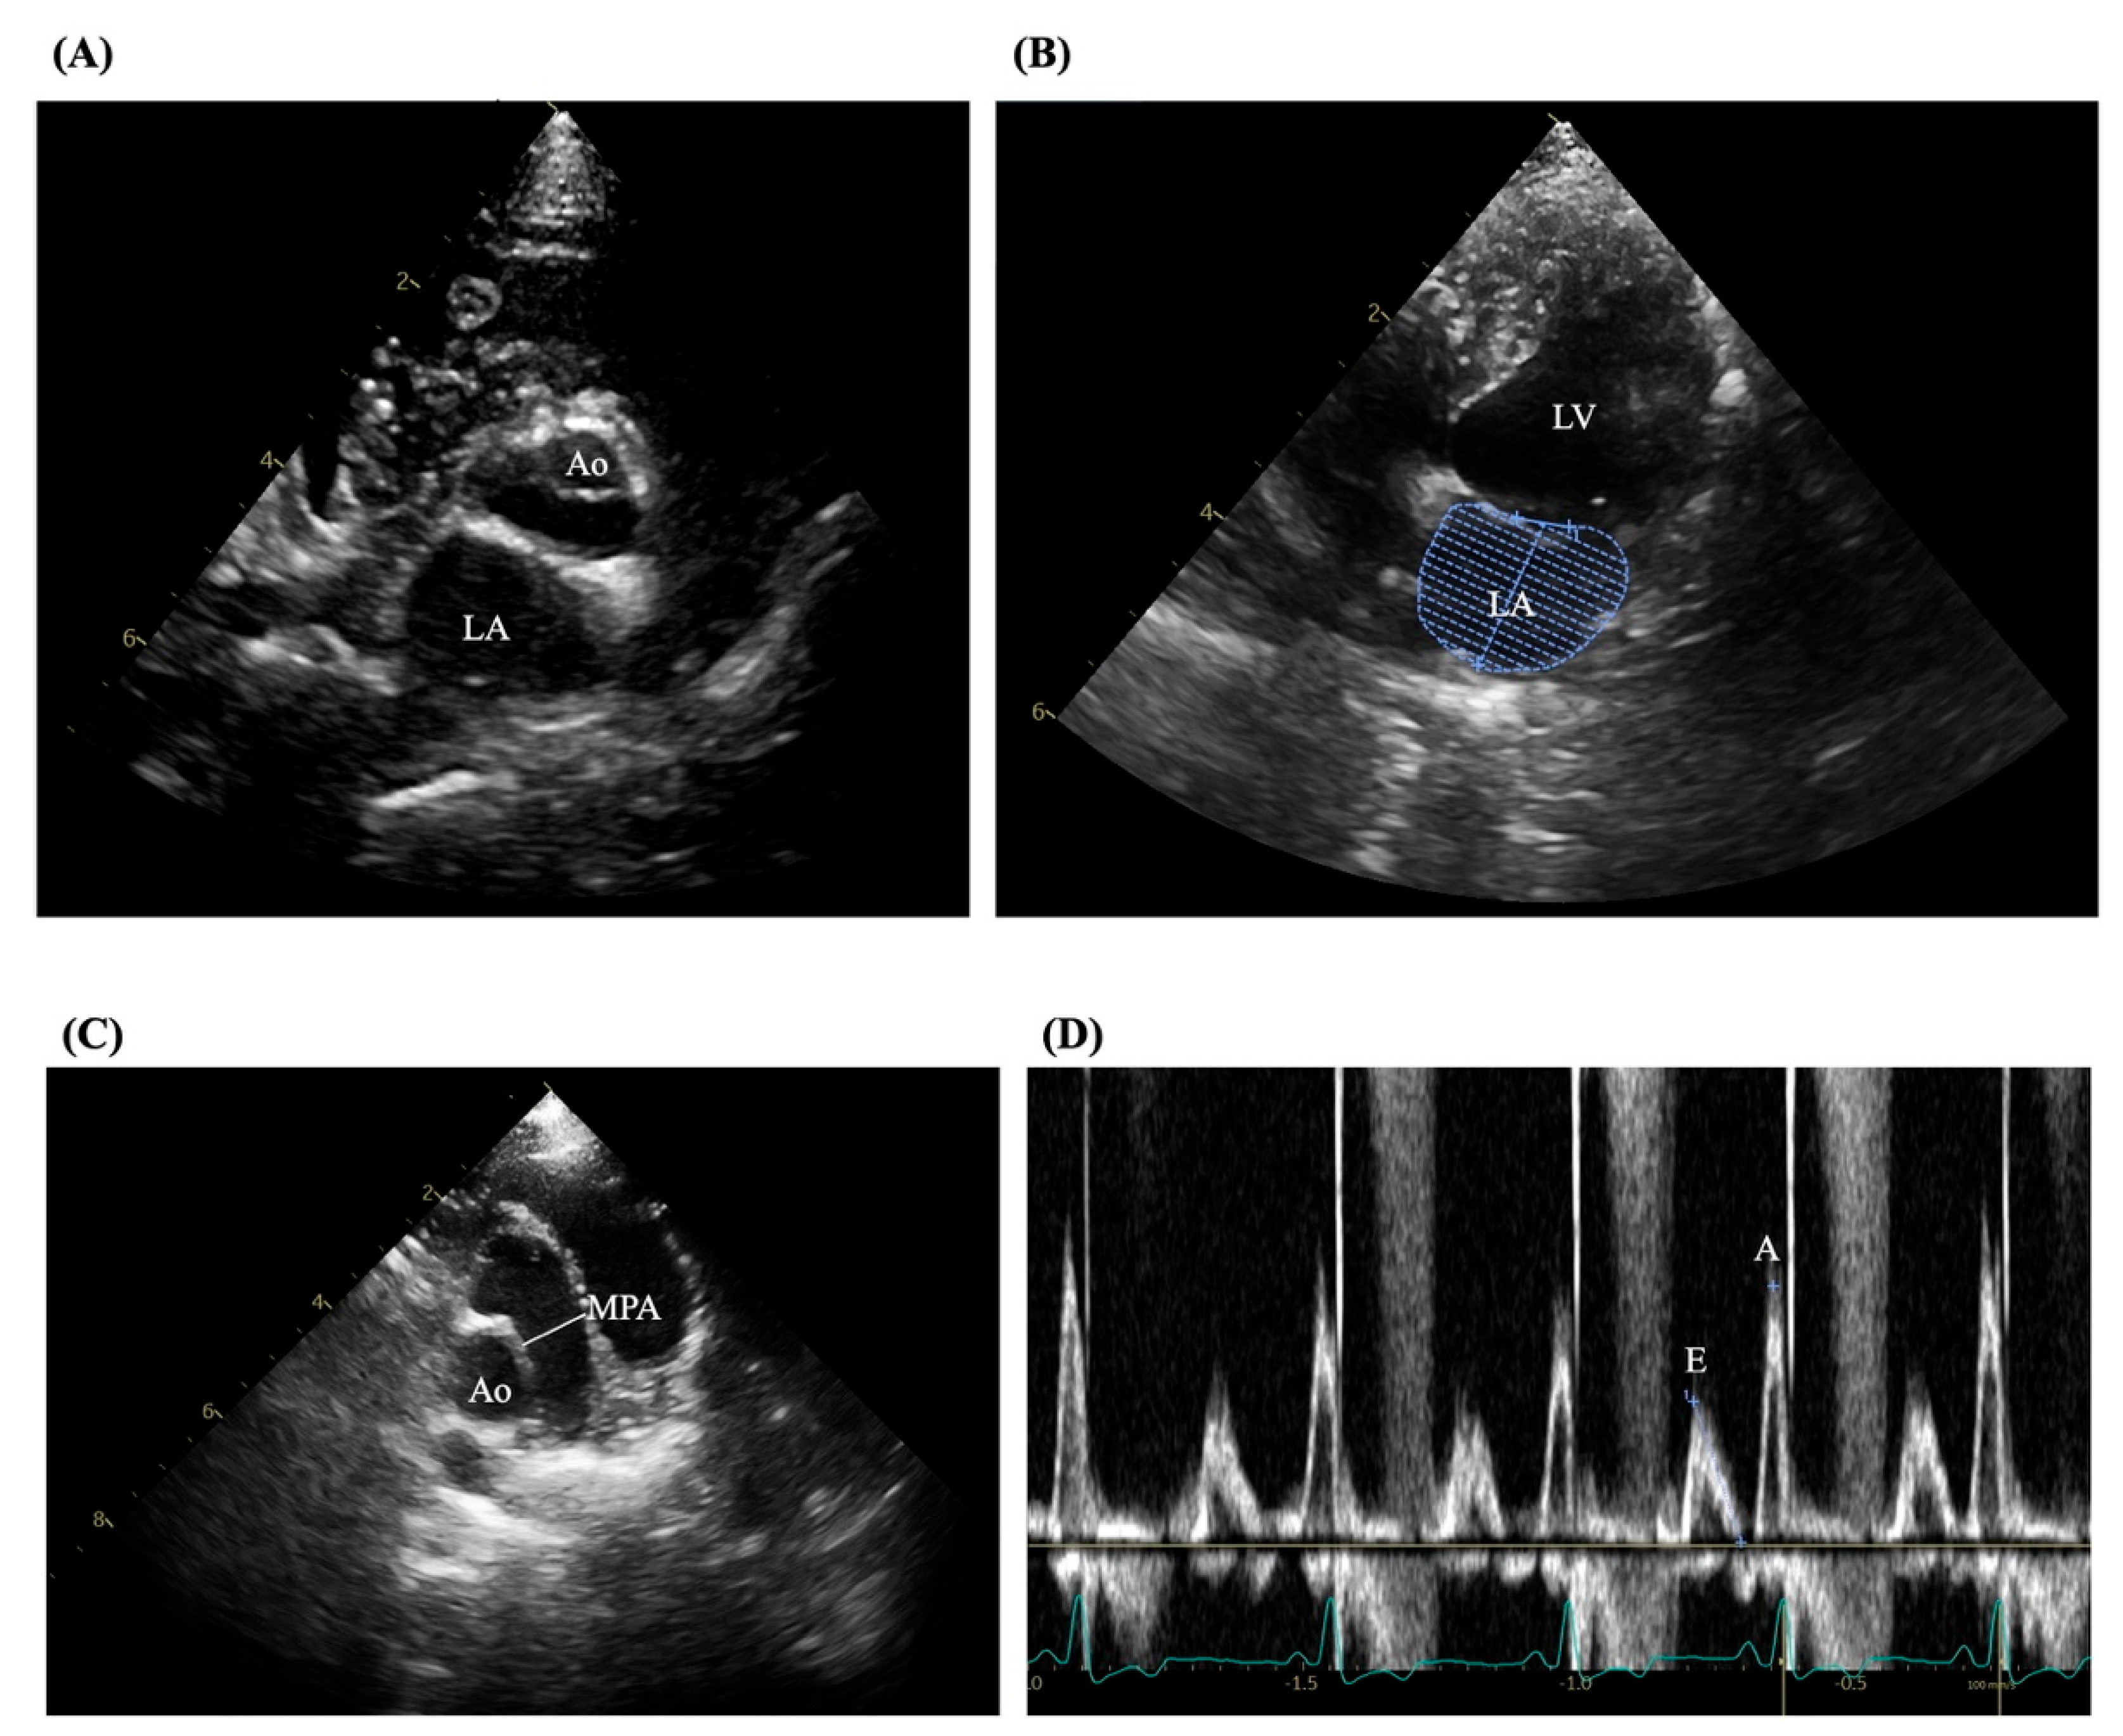

The experienced sonographers conducted echocardiography according to established guidelines to confirm mitral valve disease and exclude other cardiac disorders [23,24]. Examinations were performed using a Philips ultrasound machine (Bothell, WA, USA) equipped with 5.0–9.0 MHz phased-array transducers. All assessments followed standardized imaging protocols as outlined by the American Society of Echocardiography and utilized 2D, M-mode, color flow Doppler, and tissue Doppler imaging. Measured variables included LV internal diameters at diastole (LVIDd) and systole (LVIDs), fractional shortening (FS), LA diameter, aortic diameter (Ao), LA volume, and pulmonary artery diameter (MPA). Trans-mitral flow velocities were measured using pulsed-wave Doppler, and the E/A ratio was derived as shown in Figure 1 (A-D). Tissue Doppler imaging was applied to obtain peak velocities at the lateral mitral annulus.

Figure 1. Echocardiographic assessment in MMVD dogs. The representative figures were visualized by the 2D mode in the short-axis view (A), (B) left apical four-chamber view, (C) parasternal short-axis view at the aorta and pulmonic valve level, MPA = the main pulmonary artery diameter; LV = left ventricle, and (D) Pulsed-wave Doppler echocardiography of the transmitral flow.